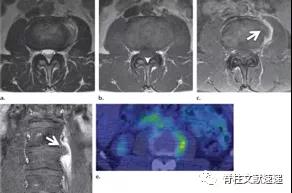

- 急性Schmorl结节作为症状或活动性炎症的一种特殊原因在影像成像中是少见的,如MR成像、PET或骨扫描。当出现这种影像学表现时,可能被误认为是其他病变,如恶性肿瘤、骨髓炎或椎间盘炎。

- PET成像不能作为评价椎间盘病变情况的主要方法。椎间盘突出,特别是急性或亚急性时,并伴有炎症反应,可导致PET局灶性FDG摄取。

图注:49岁男性,极外侧腰椎间盘突出症,有黑色素瘤病史。(e) 轴位PET图像显示病灶部位有FDG摄取,怀疑黑色素瘤转移。经过3周的保守治疗,病人的病情有所好转。临床上并没有黑色素瘤诊断。